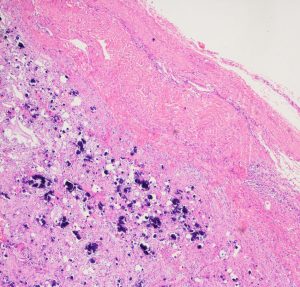

病理所見では,幼児型のpilomyxoid astrocytomaの部分が混在します。その部分が増殖と腫瘍増大に関わっています。T2強調画像で高信号でガドリニウム増強される部分です。

myxoidな部分です。右下のMIB-1染色では3%ほどの陽性率であり,数年単位では腫瘍増大があり得ることを示します。柔らかく出血性で吸引摘出できる部分の腫瘍です。IDH wild type, BRAFV600 wild type, H3K27 wild type, FGFR1 N546K mutationでした。